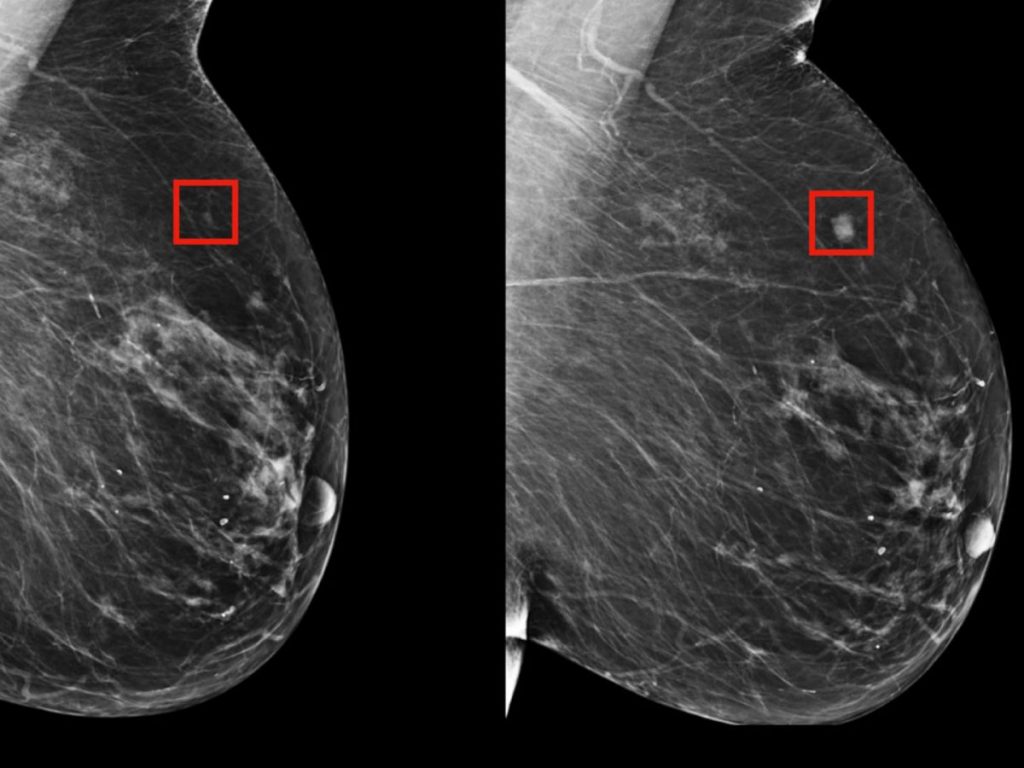

Model vyvinutý na Massachusetts Institute of Technology nehledá nádor. Hledá pravděpodobnost. Stín budoucnosti. Jemný náznak, který nekřičí, ale šeptá.